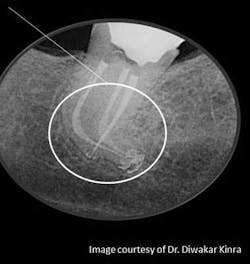

3. Comfortably numb: how dental anesthesia can differentiate your endodontic practice — In today’s economic climate, dentists are looking for ways to differentiate themselves within the community. Here, Dr. Diwakar Kinra shows you how Onset from Onpharma can be used to provide comfortable and profound anesthesia for your endodontic patients as he presents three clinical case studies.